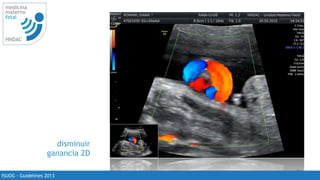

disminuir

ganancia 2D

ISUOG - Guidelines 2013